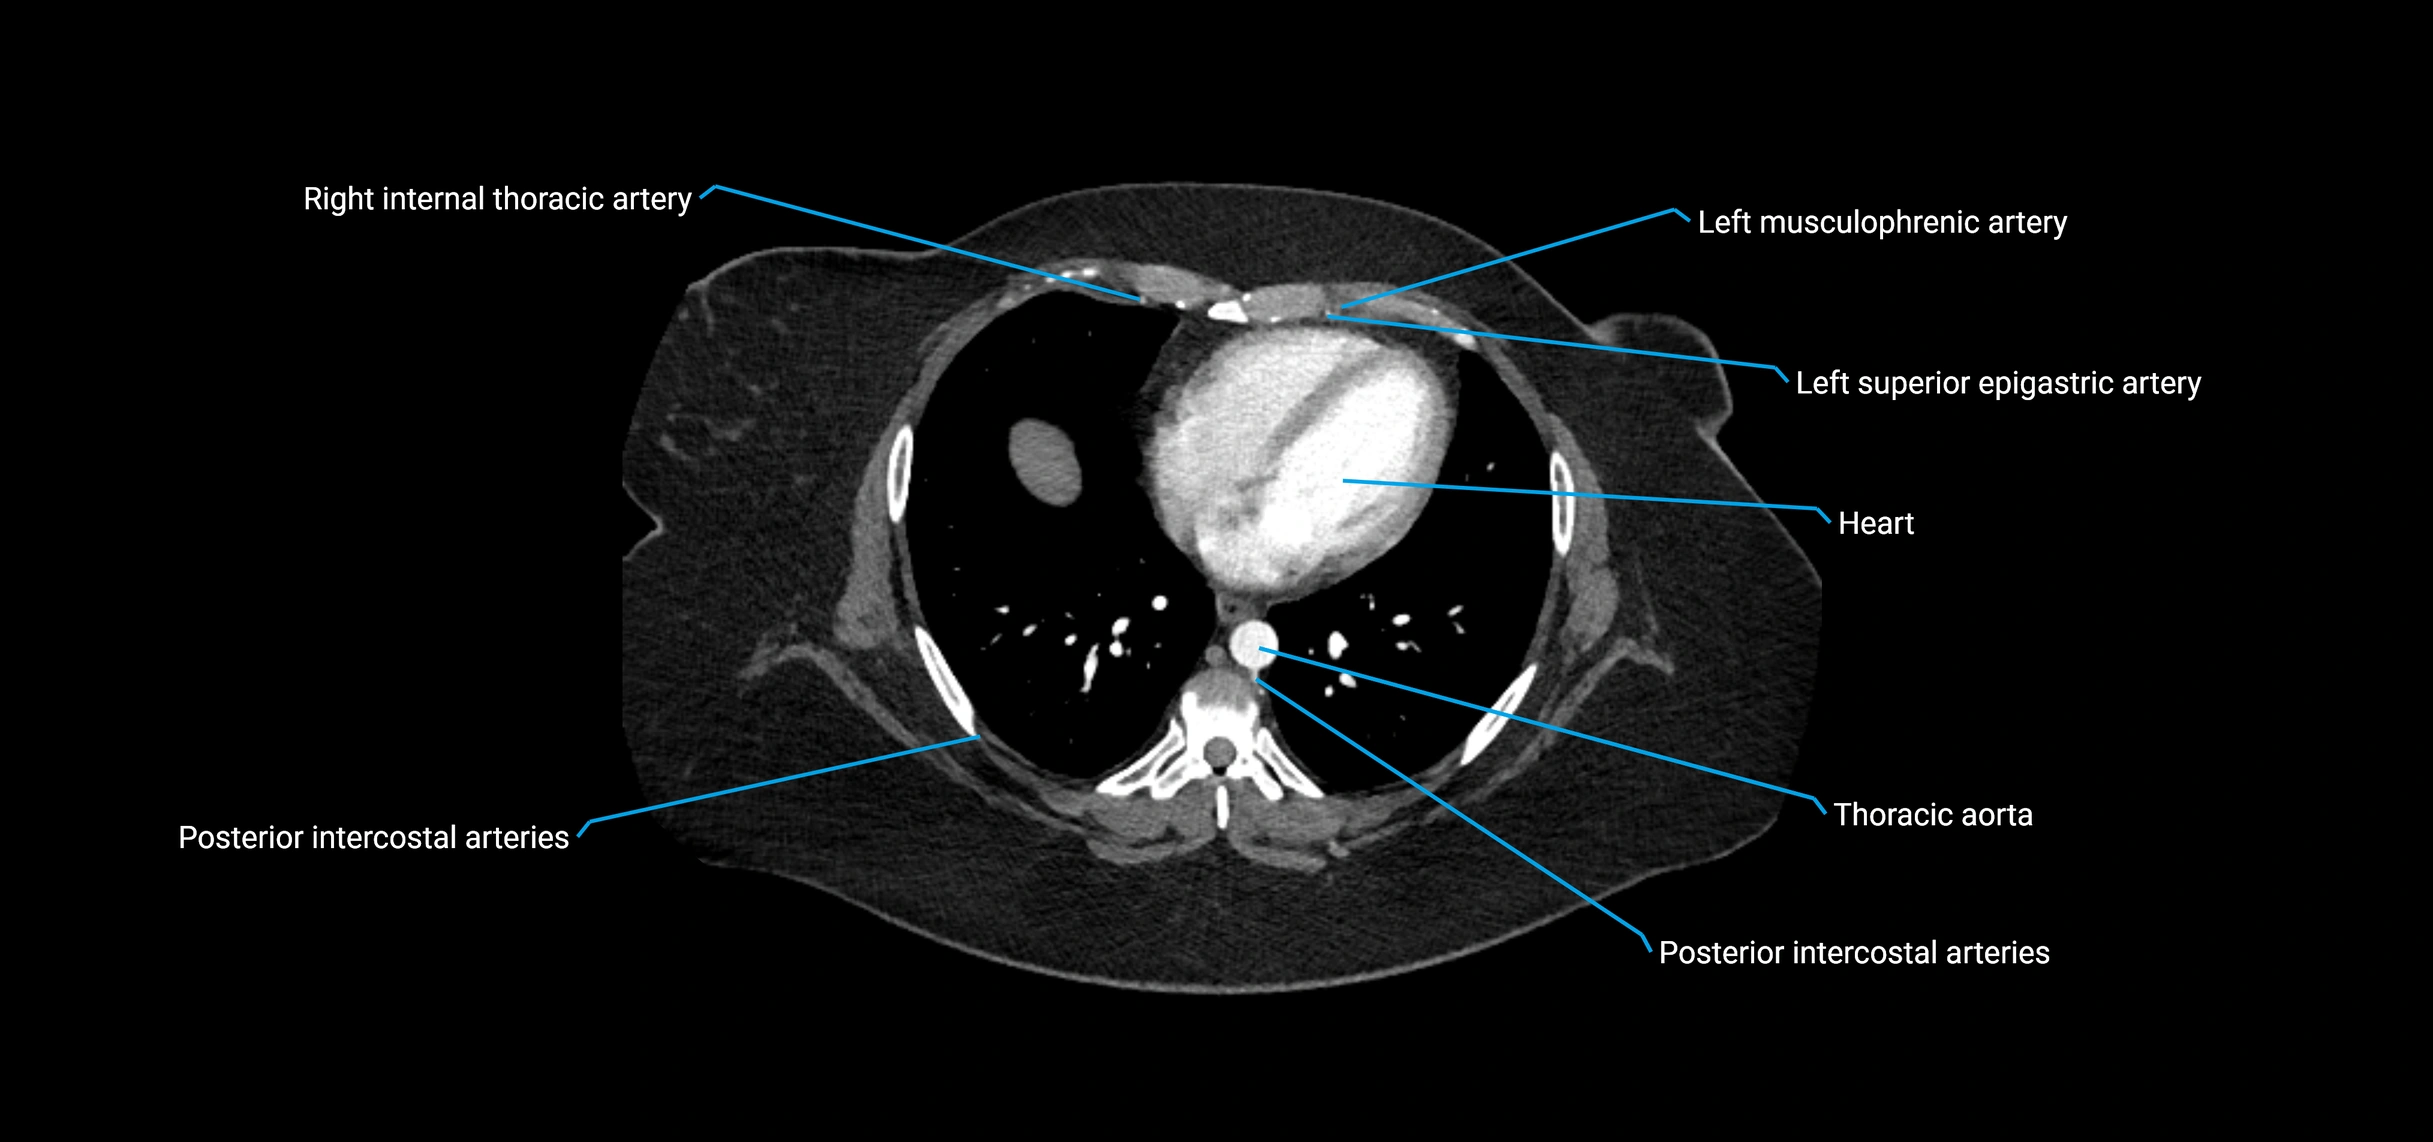

CT Appearance

Non-contrast CT:

• Appears as a tubular soft tissue structure anterior to vertebral bodies

• Calcified atherosclerotic plaques appear as hyperdense foci along the wall

• Useful for screening abdominal aortic aneurysm (AAA) size and mural calcification

Contrast-enhanced CT (CTA):

• Gold standard for abdominal aortic imaging

• Provides excellent detail of lumen, wall, aneurysm, thrombus, and branch vessels

• Multiplanar and 3D reconstructions help in aneurysm measurement, stent graft planning, and dissection evaluation

• Detects acute rupture, traumatic injury, or occlusion with high sensitivity

CT images

image